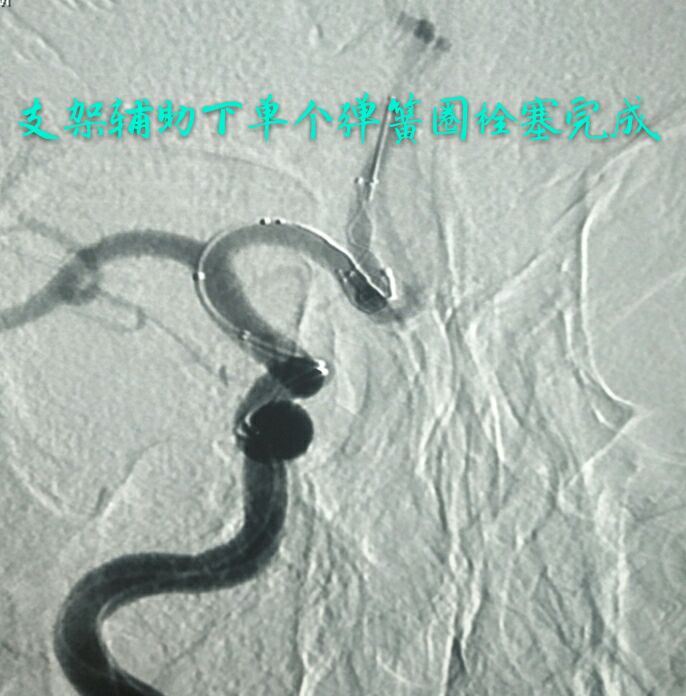

病例七:眼动脉段破裂微小动脉瘤,相对宽颈,呈锥形

支架辅助下用小弹簧圈致密栓塞动脉瘤